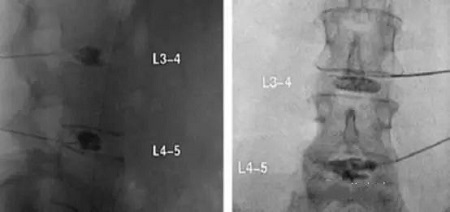

X線矢狀位和前后位L3-4和L4-5椎間盤造影術(shù)

CT軸位和前后位顯示L4-5間盤造影和血小板注射。